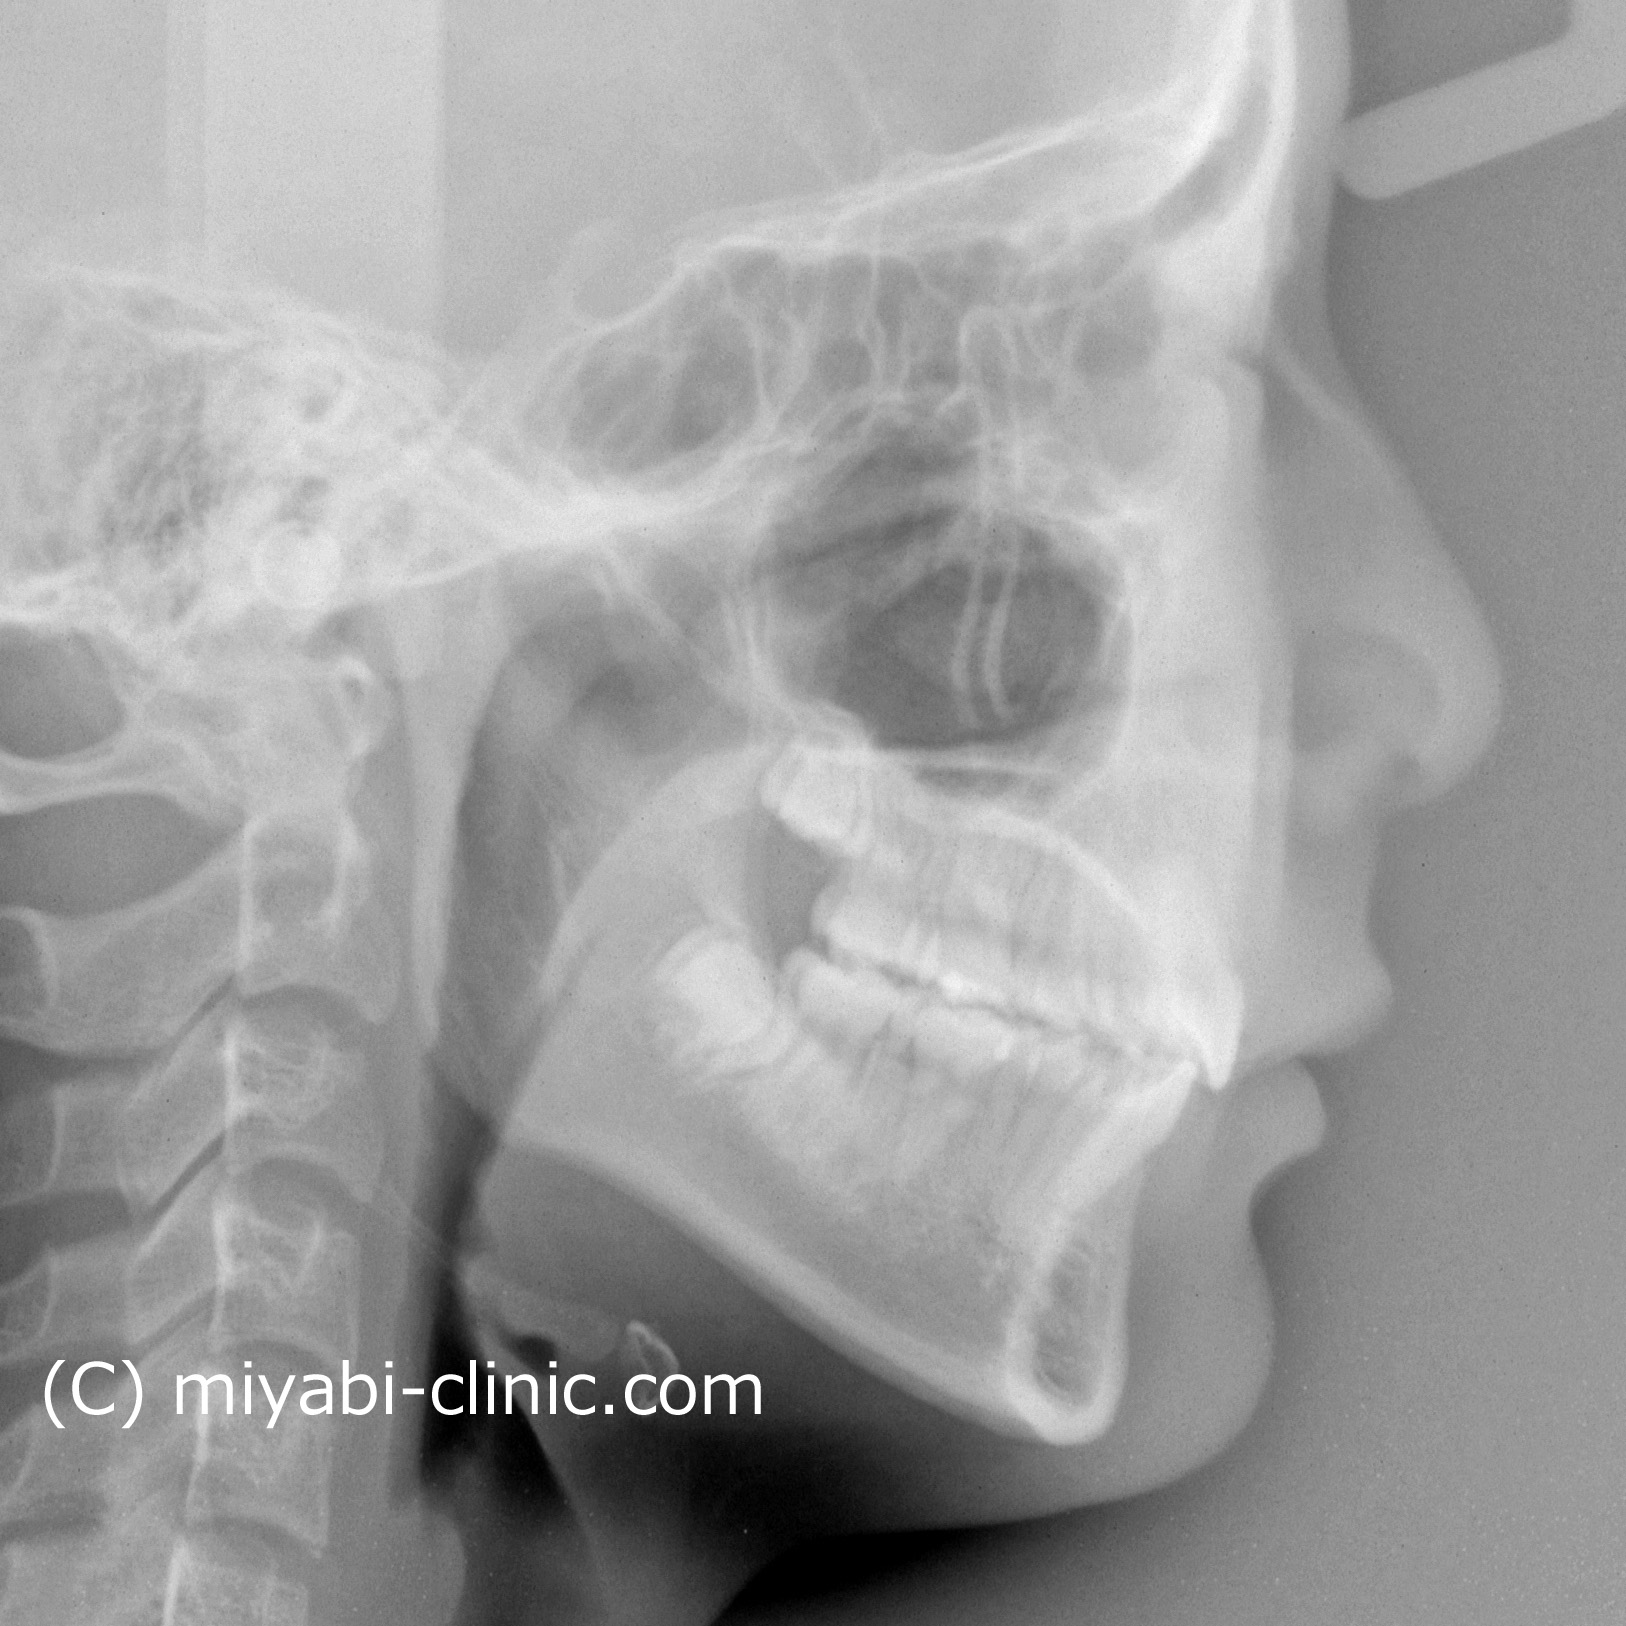

新着情報 1668 治療後セファロ側面 Tweet 投稿日 : 2025年10月19日(日)カテゴリー : コメントを残す コメントをキャンセルメールアドレスが公開されることはありません。 * が付いている欄は必須項目ですコメント 名前 * メール * サイト 1668 治療後セファロ側面 ≫